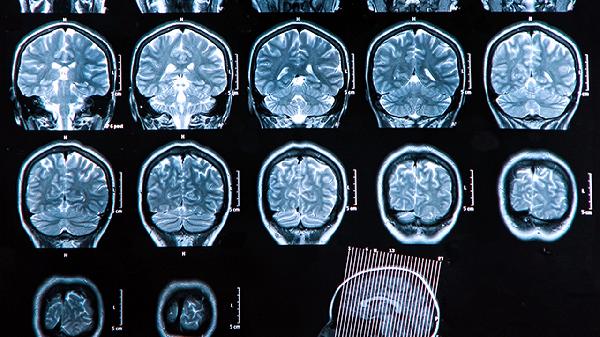

睡眠周期分为非快速眼动期和快速眼动期,梦境多发生在快速眼动期。成年人每晚经历4-6个睡眠周期,每个周期都会做梦。大脑在此时进行记忆整合、情绪调节等重要功能,属于自然的神经活动过程。杏仁核、海马体等脑区活跃度增加,有助于处理日间信息。